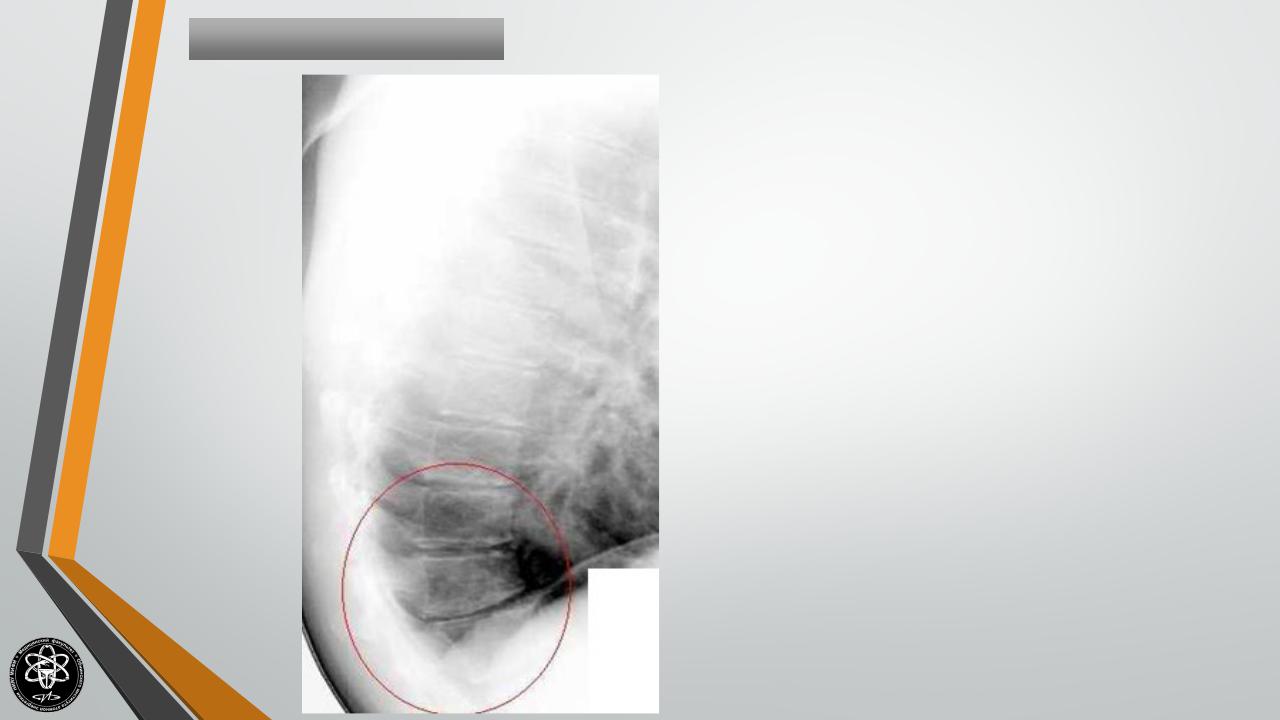

Остеохондропатия апофизов позвонков (чаще Th7- |

Болезнь Шоермана-Мау |

Th10). Распространенная патология. Возникает в |

подростковом возрасте, чаще у мальчиков. |

Сопровождается кифозом средне- и нижнегрудного |

отдела позвоночника (круглая спина). Боли могут |

быть слабыми или вовсе отсутствовать. Иногда |

единственным поводом для обращения к ортопеду |

становится косметический дефект. |

Диагностика |

остеохондропатии |

осуществляется при помощи рентгенографии и КТ |

позвоночника. |

Дополнительно |

состояния спинного мозга и связочного аппарата позвоночного столба проводят МРТ позвоночника.

Остеохондропатия поражает несколько позвонков и сопровождается их выраженной деформацией, остающейся на всю жизнь. Для сохранения нормальной формы позвонков больному необходимо обеспечить покой. Большую часть дня пациент должен находиться в постели в положении на спине. Больным назначают массаж мышц живота и спины, лечебную гимнастику. При своевременном, правильном лечении прогноз благоприятный.